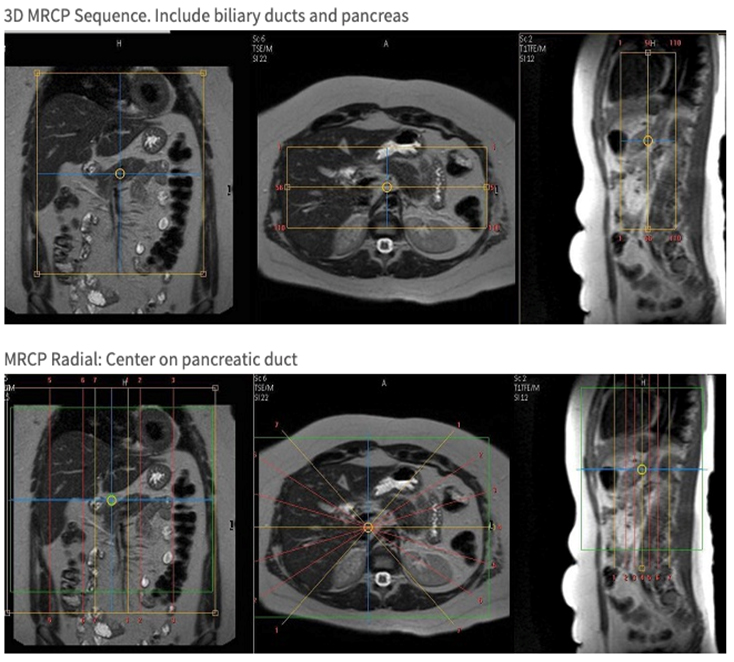

Cor T2 3D MRCP 1.4mm Y Bottom 2/3 of liver through bottom of pancreas Please use navigator trigger & track.

Cor T2 Radial MRCP 12mm Y Liver through bottom of kidneys Please use navigator trigger & track. 12Slices @ ~30 degree intervals.